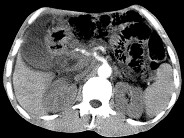

单项选择题女,50岁, 中上腹疼痛,消瘦乏力, 影像检查如下图,最佳的诊断为( )

A、胰岛素瘤

B、慢性胰腺炎

C、急性胰腺炎

D、腹膜后淋巴瘤

E、胰腺癌并腹膜后淋巴结转移